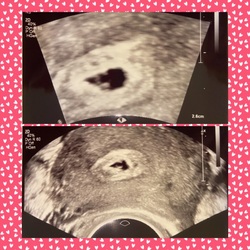

Na de 1e echo maar eens gaan kijken dinsdag want t is echt niet meer te doen ... 😫